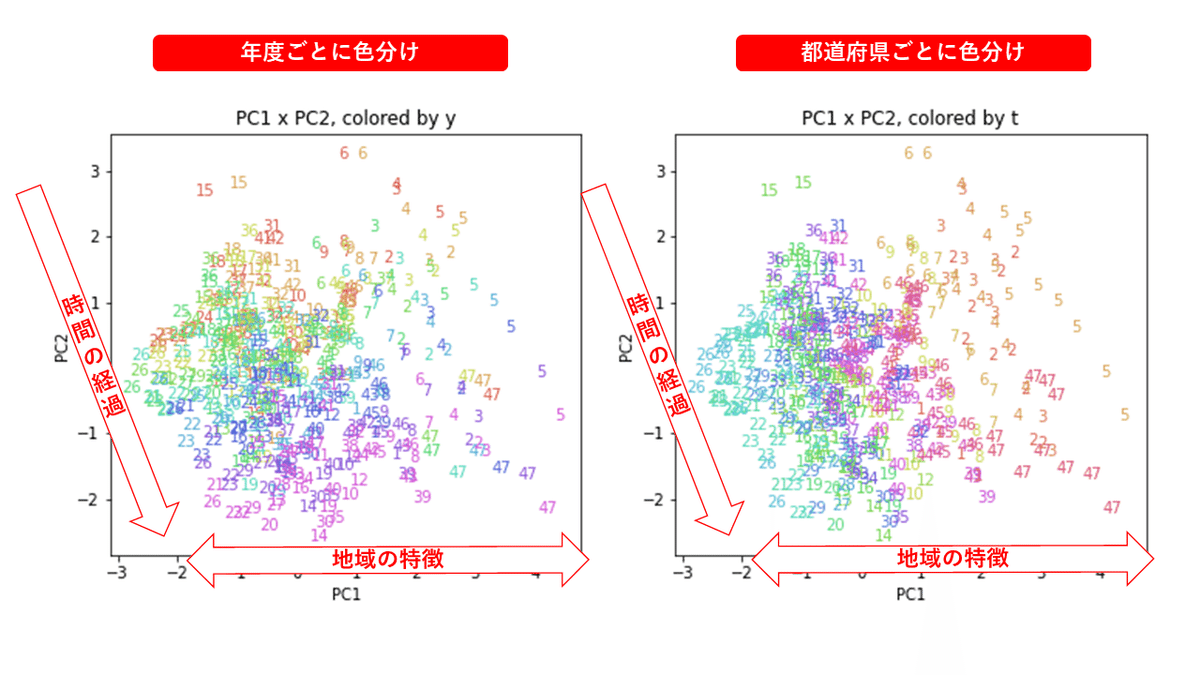

PCAの結果の第n主成分をPCnと表記します。

医療費データの場合と同様に、PCAの結果を見やすく表示するため、seabornのカラーパレットを使って、年月別、都道府県別に色分けして図示してみます(左側が年月別に色分け、右側が都道府県別に色分け)。PC1~PC8まで表示しました。

都道府県番号の表示

上の色分けだけでは都道府県が区別しにくいので、医療費データの場合と同様に、点の代わりに都道府県番号をプロットした図も描いておきます(色分けは上と同じ)。

医療費データの場合ほどはっきりとはしていませんが、PC2が概ね時間の経過を表す成分で、残りの成分が時点によって変わらない地域の特徴を表す成分となっているようです。

また、PC1×PC3を見ると、47沖縄が他の都道府県からかなり離れたところに位置しており、沖縄の地域差が際立っているのが分かります。これは、以前別の記事で年齢階級のない健診データでPCAを実行した場合と似た結果となっています。

今回は、医療費データと同様に、健診データ240次元についてPCAを実行してみました。PCAの結果、医療費データの場合ほどはっきりしとはしていませんが、第2主成分が概ね時間の経過を表す成分で、時間軸に沿った全体的な動き(全国的な動き)を表しており、それ以外の成分が地域の特徴を表す成分で、この10年間あまり変わっていないことがわかりました。